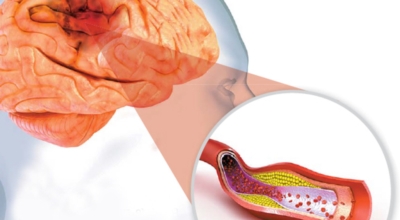

전 세계적으로 2초에 한명씩 발생하고, 6초에 한 명씩 사망하는 질병으로 국내에서도 3대 사망 이유가 되는 것 중 하는 뇌졸중. 뇌졸중은 뇌 일부분에 혈액을 주는 혈관이 막히거나 터지면서 발생하는 병으로 고혈압이 뇌졸중의 대표적인 까닭 질환입니다. 뇌졸중은 뇌혈관이 막히거나 터져서 뇌세포가 훼손되서 생기는 신경학적 증상입니다.

뇌졸중은 뇌경색과 뇌출혈 두가지로 나뉘게 돼요. 먼저 뇌경색은 뇌혈관이 막혀 영양분과 산소를 주는 피가 통하지 않는 상태로 원은은 크게 세 가지로 나눌 수 있는데요 동맥경화증이 생겨 좁아진 부위로 인하여 혈액공급이 부족해지거나 좁아지다가 결국 막혀버리는 경우, 큰 혈관에서 분지한 작은 혈관들이 고혈압 등으로 압박을 받으면 혈관이 막히는 경우가 있습니다.

또한 심장 판막질환이나 심방세동 또는 심근병 등등의 심장 질환이 있는 경우 심장에서 혈전이 만들어지고 그게 뇌로 흘러가게 되면 뇌혈관을 막게 되는 경우가 있답니다. 뇌출혈은 뇌경색과 반대로 뇌혈관이 터져서 생기는 뇌내 출혈과 거미막하 출혈로 나누게 돼요. 거미막하출혈은 혈관벽의 약한 부분이 부풀어 오르는 뇌동맥류가 터지는 경우와 관련성이 크다고 해요.